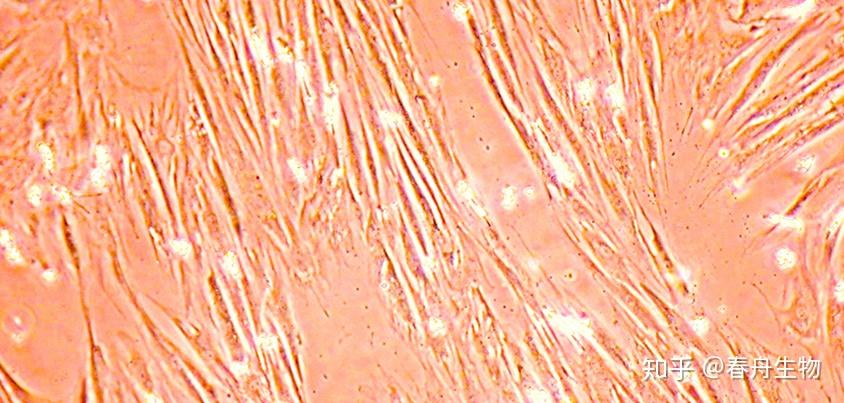

增殖中的牙髓干细胞